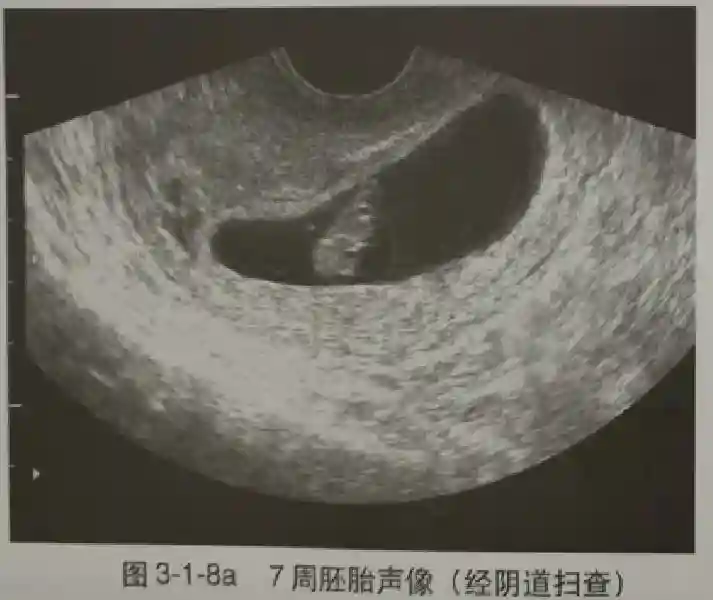

3??胚胎:胚胎通常在6-7周时可以为超声显示,起初为胎芽,表现为卵黄囊一侧局部组织增厚,达到1 -2 mm 时才有可能为超声测量出来。达4-5mm时可见胎心搏动,相应孕周为6-6.5周,妊娠囊大小为13-18mm。胚芽长度≥7㎜时仍未见心管搏动,提示胚胎停止发育。胚胎的出现和妊娠囊直径的关系:妊娠囊直径> 16 mm 时,经阴道超声应显示胚胎。妊娠囊直径> 25 mm 时,经腹超声均应显示胚胎。

5??羊膜:早孕期羊膜囊菲薄,超声常不能显示。孕7周以后加大增益或者用高频超声可以显示羊膜。羊膜囊位于绒毛膜内,胚胎位于羊膜囊内。随着胚胎增长,羊水增多,羊膜囊增大,孕12-16周时,羊膜与绒毛膜全部融合,胚外体腔消失。宫腔线一侧内膜内一圆形增强回声区,中央有小囊状液性暗区,宫腔线局部突起变形,称蜕膜内征,用于判断早早孕。